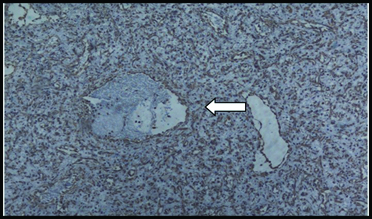

Histopatholgy revealed: Thin walled blood vessels surrounded by fibrous stroma. The blood vessels were lined by a single layer of endothelial cells and incomplete muscular walls [Table/Fig-3]. The following histopathological differential diagnoses were made: Capillary haemangioma, Haemangiopericytoma, Solitary fibrous tumour and Angiofibroma. To confirm the diagnosis immunohistochemistry was done. Immunohistochemistry (IHC) showed vimentin positive stromal cells, SMA positive in cells around vascular spaces and CD34 positivity in vascular endothelial cells [Table/Fig-4,5 and 6] consistent with angiofibroma. Thus a final diagnosis of Extranasopharyngeal Angiofibroma (ENA) of the inferior turbinate was made. The case is in regular follow-up with us for the past one year with no recurrence or any untoward incident to report.

400X. H&E: Variable sized vascular spaces in fibrous stroma.

100X. Vimentin positive in stromal cells (arrow).